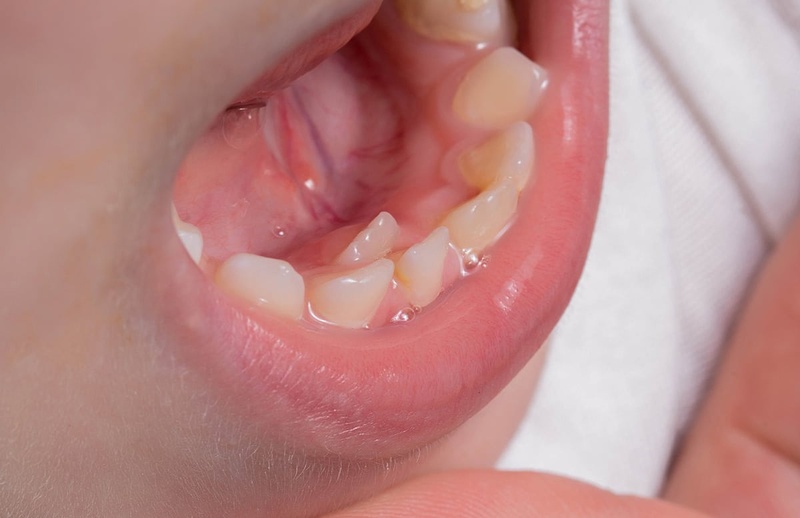

- Chậm mọc răng vĩnh viễn: Đây là dấu hiệu quan trọng ở trẻ em. Răng thừa đặc biệt là răng ngầm có thể cản đường, khiến răng vĩnh viễn (nhất là răng cửa) mọc lên rất muộn hoặc không mọc được.

- Răng sữa rụng muộn: Tương tự, răng thừa có thể kẹt giữ răng sữa, làm răng sữa không rụng theo đúng lịch trình.

- Chậm mọc răng: Răng thừa là nguyên nhân phổ biến nhất gây chậm mọc hoặc mọc lệch lạc của răng vĩnh viễn. Tình trạng này đặc biệt hay gặp ở răng cửa hàm trên/ dưới của trẻ em.